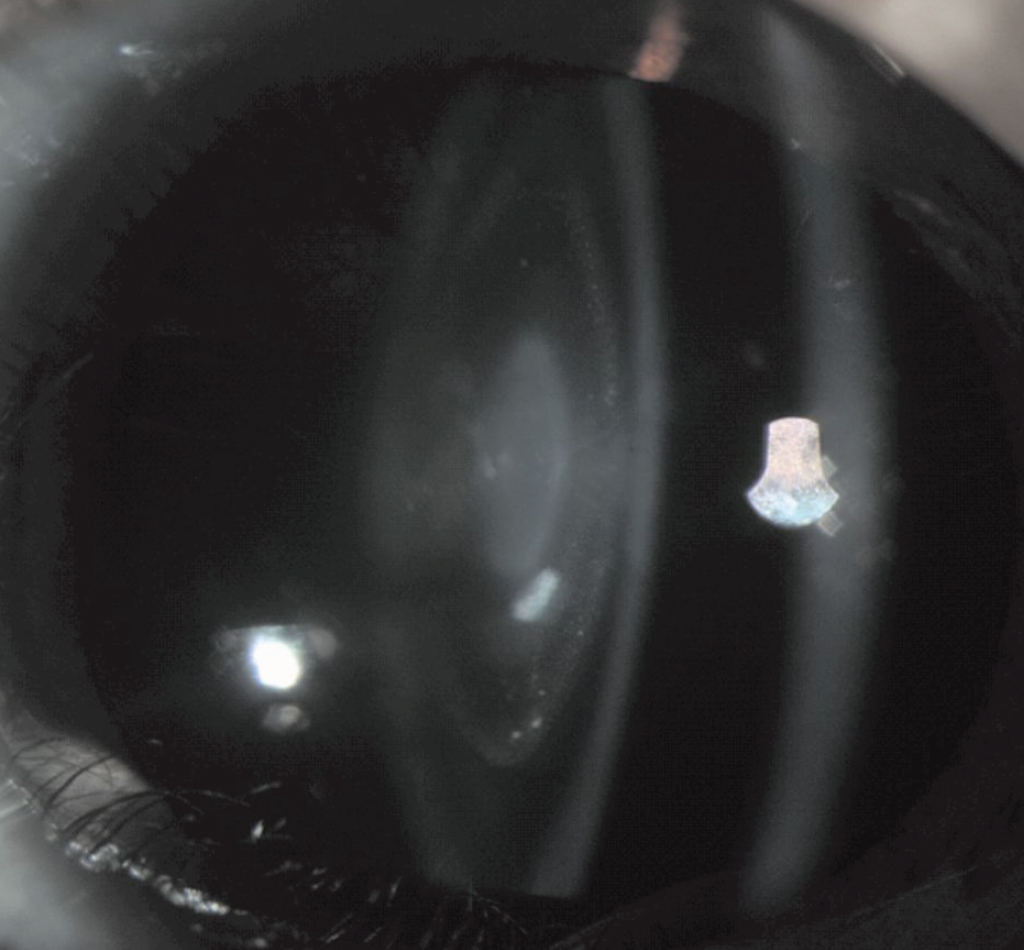

Figure 2. Slit-lamp photograph of the proband. It showed a cataract characterized as a central nuclear opacity of the lens with punctiform opacities.